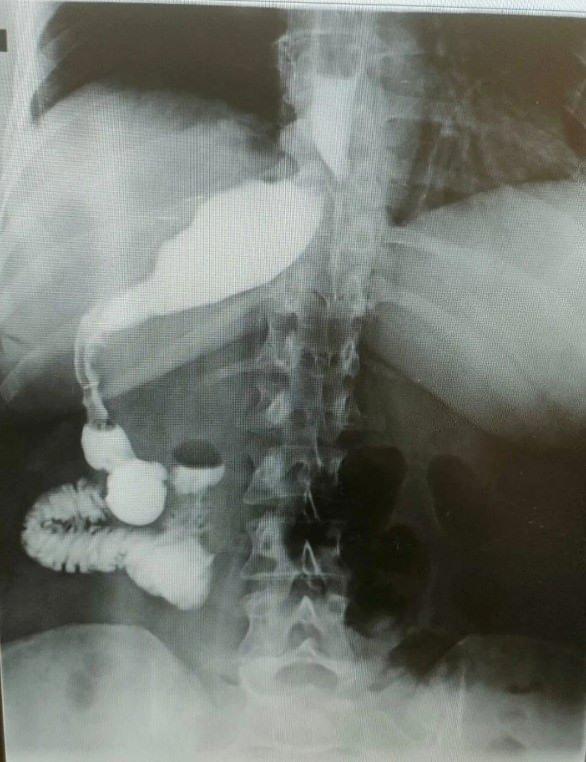

Ameliyat esnasında cerrahi grup, Kirscht’in midesini karaciğerinin ardında, sağ tarafta buldu. Bu sıra dışı anatomik durum, hem hasta hem de grubun şaşkınlık yaşamasına neden oldu.

100 binde bir görüldüğüne dikkat çeken doktor, “Organların hepsi ters olabiliyor. Bu daha sık görülen bir şey lakin bu hastada bütün organlar yerli yerinde fakat yalnızca mide sağ tarafa kaymış. Yani karaciğerin ardına gitmiş.” dedi.

Operasyona başlanıldığında mideyi bulamadıklarını lisana getiren doktor, “Karaciğeri kaldırınca mideyi sağ tarafta gördük. Bu çok az bir durum. 2023 yılı bilgilerine nazaran, bu türlü bir tüp mide ameliyatı dünyada sadece 50 bireye uygulanmış. Biz de bu hadiseyi muvaffakiyetle gerçekleştirdik. Teknik açıdan bizi zorlayan lakin tecrübemizi artıran bir ameliyat oldu”. diye konuştu.